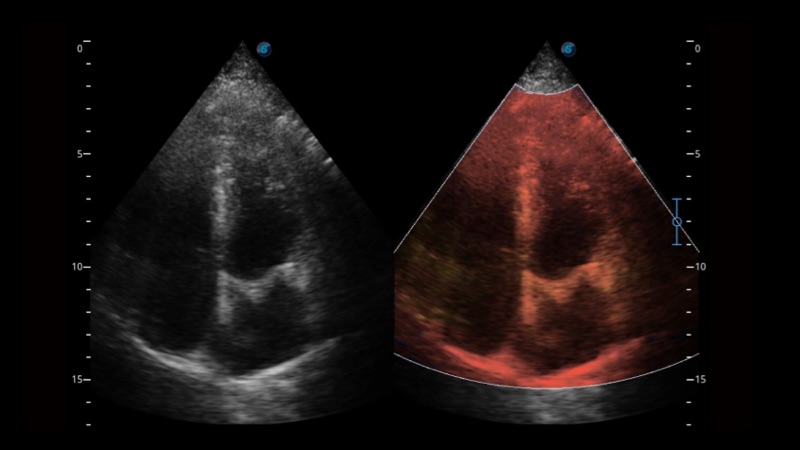

開立醫(yī)療通過不斷的技術(shù)創(chuàng)新,為大眾的生命健康提供持續(xù)關(guān)愛。P12 Plus采用全新一代超聲成像平臺,新平臺旨在將真實(shí)還原組織解剖結(jié)構(gòu)作為首要目標(biāo)。平臺采用全新集成化硬件模塊,搭載新一代芯片,系統(tǒng)性能得到大幅提升,為您的診斷提供了豐富的臨床信息。優(yōu)異的圖像表現(xiàn),豐富的探頭配置,全面的應(yīng)用功能,為您日常診斷提供了可靠的助手。